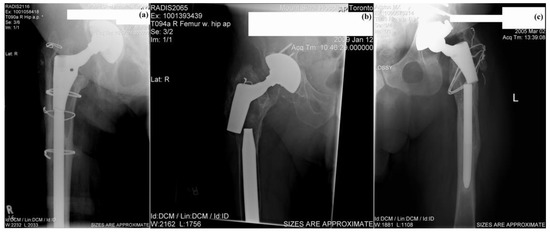

At Tel-Aviv University, we have used Bio-Ferrography to isolate particles suspended in synovial fluids for evaluation of artificial hip and knee joints performance. Synovial fluid aspirates and prosthesis compartments removed by revision surgery from 14 patients were analysed. Results showed that metallic (namely, Ti-, Co- and Fe-based alloys), polymeric (ultrahigh molecular weight polyethylene—UHMWPE, polyoxymethylene—POM, and poly(methyl methacrylate)—PMMA) and bone particles were suspended in synovial fluids. The formation of metal, PMMA and bone particles seemed to further accelerate the wear of certain prostheses. Figure 4a provides a macroscopic view of a failed hip prosthesis. This type of cementless isoelastic prosthesis was designed to reduce stress shielding of the proximal femur. The stem is made of POM, the acetabular cup of UHMWPE, and the ball and neck component from 316L stainless steel. In addition, four bone screws made of 316L stainless steel and a wire made of Ti–6Al–4V are noticed in Figure 4a. One of the screws fractured in vivo. Failure analysis revealed ductile tearing of the UHMWPE, as well as crazing and microvoid coalescence in the POM component. Pitting and wear were noticed in the neck component (Figure 4b,c). Energy dispersive X-ray spectroscopy (EDS) analysis revealed traces of chloride in these pits. Transgranular stress corrosion cracking (TG-SCC) and wear were identified around the fracture surface of the failed screw (Figure 4d,e). The exposure of grain boundaries to the outer surface of the screw indicates that the threads were fabricated by machining and not by plastic forming. This could have made them susceptible to failures by mechanisms such as SCC and fatigue [120]. Surprisingly, FDA guidelines do not include a requirement for manufacturing of threads of bone screws by cold forming, although this is a common knowledge and requirement for critical aircraft screws, for example. Numerous metallic wear particles were observed on the ferrogram under an optical microscope with bichromatic illumination (Figure 4f). Scanning electron microscope (SEM)/EDS analysis showed that 316L stainless steel, POM and bone particles were all suspended in the synovial fluid. The stainless steel particles were mainly in the form of platelets with a smooth surface and no striation marks (Figure 4g). Thus, the failure of the implant was attributed to the synergistic effect of corrosion and wear. This high amount of wear particles suspended in the synovial fluid of an alloy containing both Ni and Cr could alert on the issues of biocompatibility concerned with the use of such a metallic biomaterial. This example demonstrates the potential attractiveness of Bio-Ferrography in the study of implant degradation in vivo.